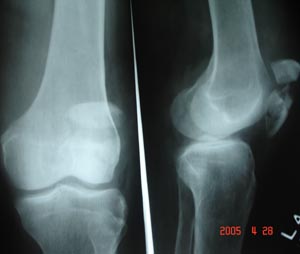

Fracture patella

This is seen in routine AP/Lat. View. But specialized view like lateral view with knee joint flexed, can locate the fracture beautifully.